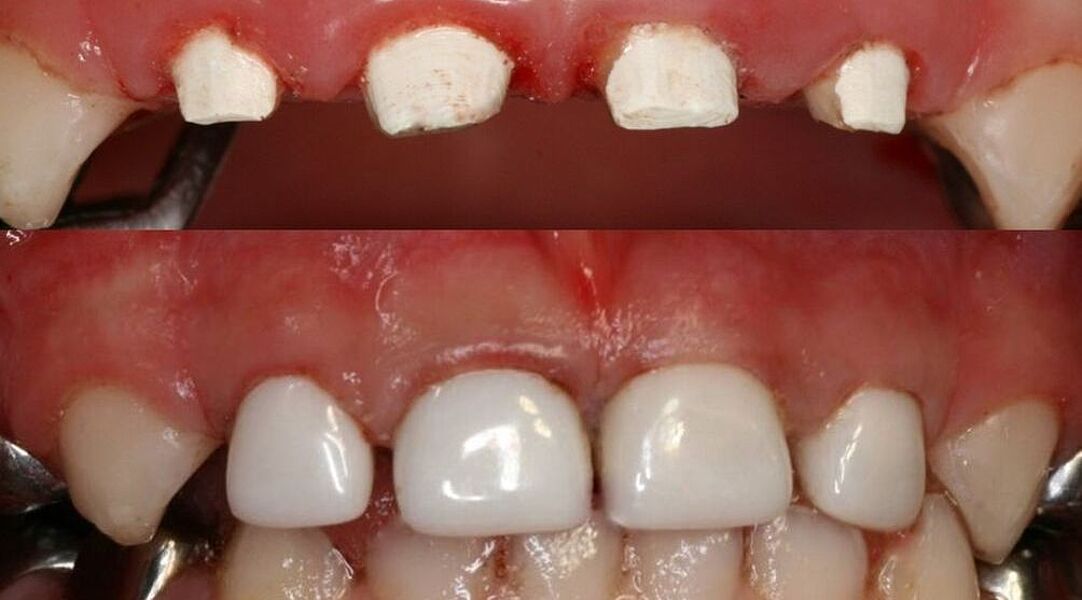

Dieses Milchgebiss wurde fachgerecht saniert. Die Karies ist verschwunden. Die Milchzähne werden erhalten, bis sie von den bleibenden Zähnen ersetzt werden. Dafür wurden auch Milchzahnkronen eingesetzt. Jetzt sind beste Bedingungen für eine effiziente Prophylaxe gegeben.